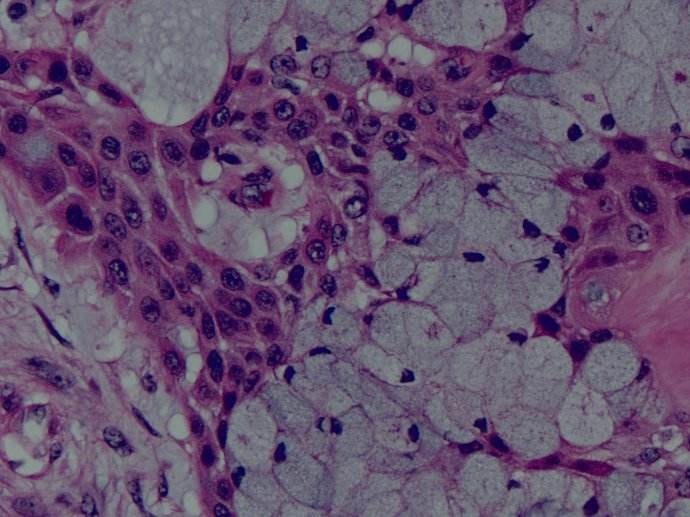

粘液表皮樣癌(mucoepidermoid carcinoma)也稱粘液表皮樣腫瘤(mucoepidermoid tumor),在涎腺腫瘤中占5%~10%。Stewart等根據(jù)其臨床特點和組織學(xué)特征將其稱為粘液表皮樣腫瘤,并又分為良性及惡性兩類。WHO也曾采用粘液表皮樣瘤的名稱,但以后許多學(xué)者認(rèn)為這種命名分類并不恰當(dāng),認(rèn)為此腫瘤全部為惡性,應(yīng)稱為粘液表皮樣癌,并根據(jù)癌細(xì)胞分化程度的高低和生物學(xué)行為,將其分為低度惡性和高度惡性粘液表皮樣癌。WHO1990年修訂的涎腺腫瘤的命名及分類已采用這種分類方法。雖然“粘液表皮樣”一詞并不完全合適,但基本上反映了腫瘤的主要成分為粘液樣細(xì)胞和表皮樣細(xì)胞。粘液表皮樣癌來源于腺管的上皮細(xì)胞。